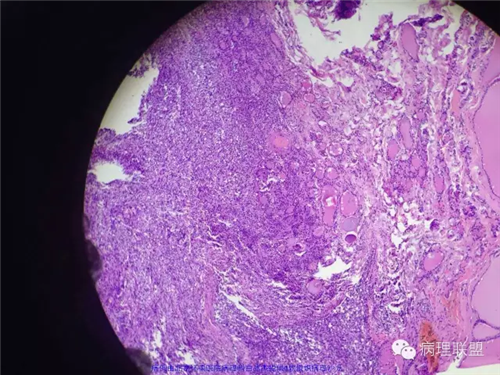

甲状腺肿物,镜下梭形细胞肿瘤,伴坏死及钙化,侵犯横纹肌及涎腺,不知道各位老师考虑什么,免疫组化还没有方向,低分化恶性梭形细胞肿瘤?炎性肌纤维母细胞肿瘤?甲状腺原发还是涎腺原发?谢谢。

好吧 俺也瞎叨叨几句:1,这一例的关键是确定和甲状腺的关系。虽然大体以及描述都说的是甲状腺,但图中没示任何甲状腺。如果找到正常甲状腺组织,当然可以;如果找到其他甲状腺高分化癌的成分,也有提示意义,2,临床表现,80岁,先倾向于UTC了;如果生长再迅速一点,那更支持了。3.镜下,UTC的几个特点(i) widely invasive growth, (ii) extensive tumor necrosis, (iii) marked nuclear pleomorphism, and (iv) high mitotic activity. 此处的坏死,是geographic coagulative necrosis,所以俺才说是有特点。